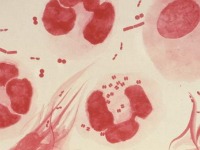

Descubren las mutaciones de una bacteria resistente.

Descubrimientos

Expertos hallan primera cepa de gonorrea calificada de ´superbacteria´

Ciencia y tecnología